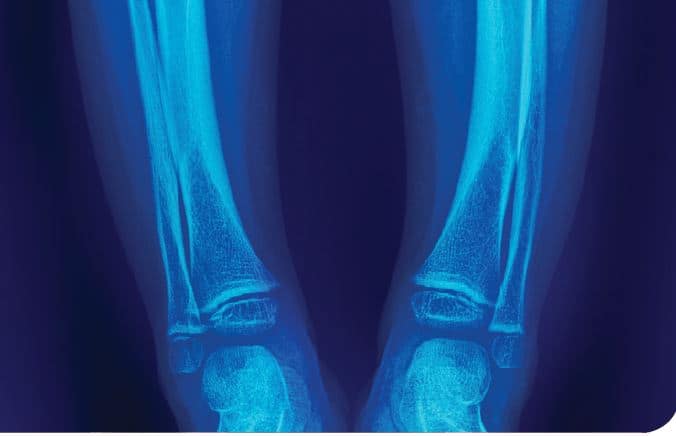

Lee sobre diagnóstico diferencial del raquitismo hipocalcémico, síndrome de hipoglicemia autoinmune, enfermedad de Huntington y mucho más.